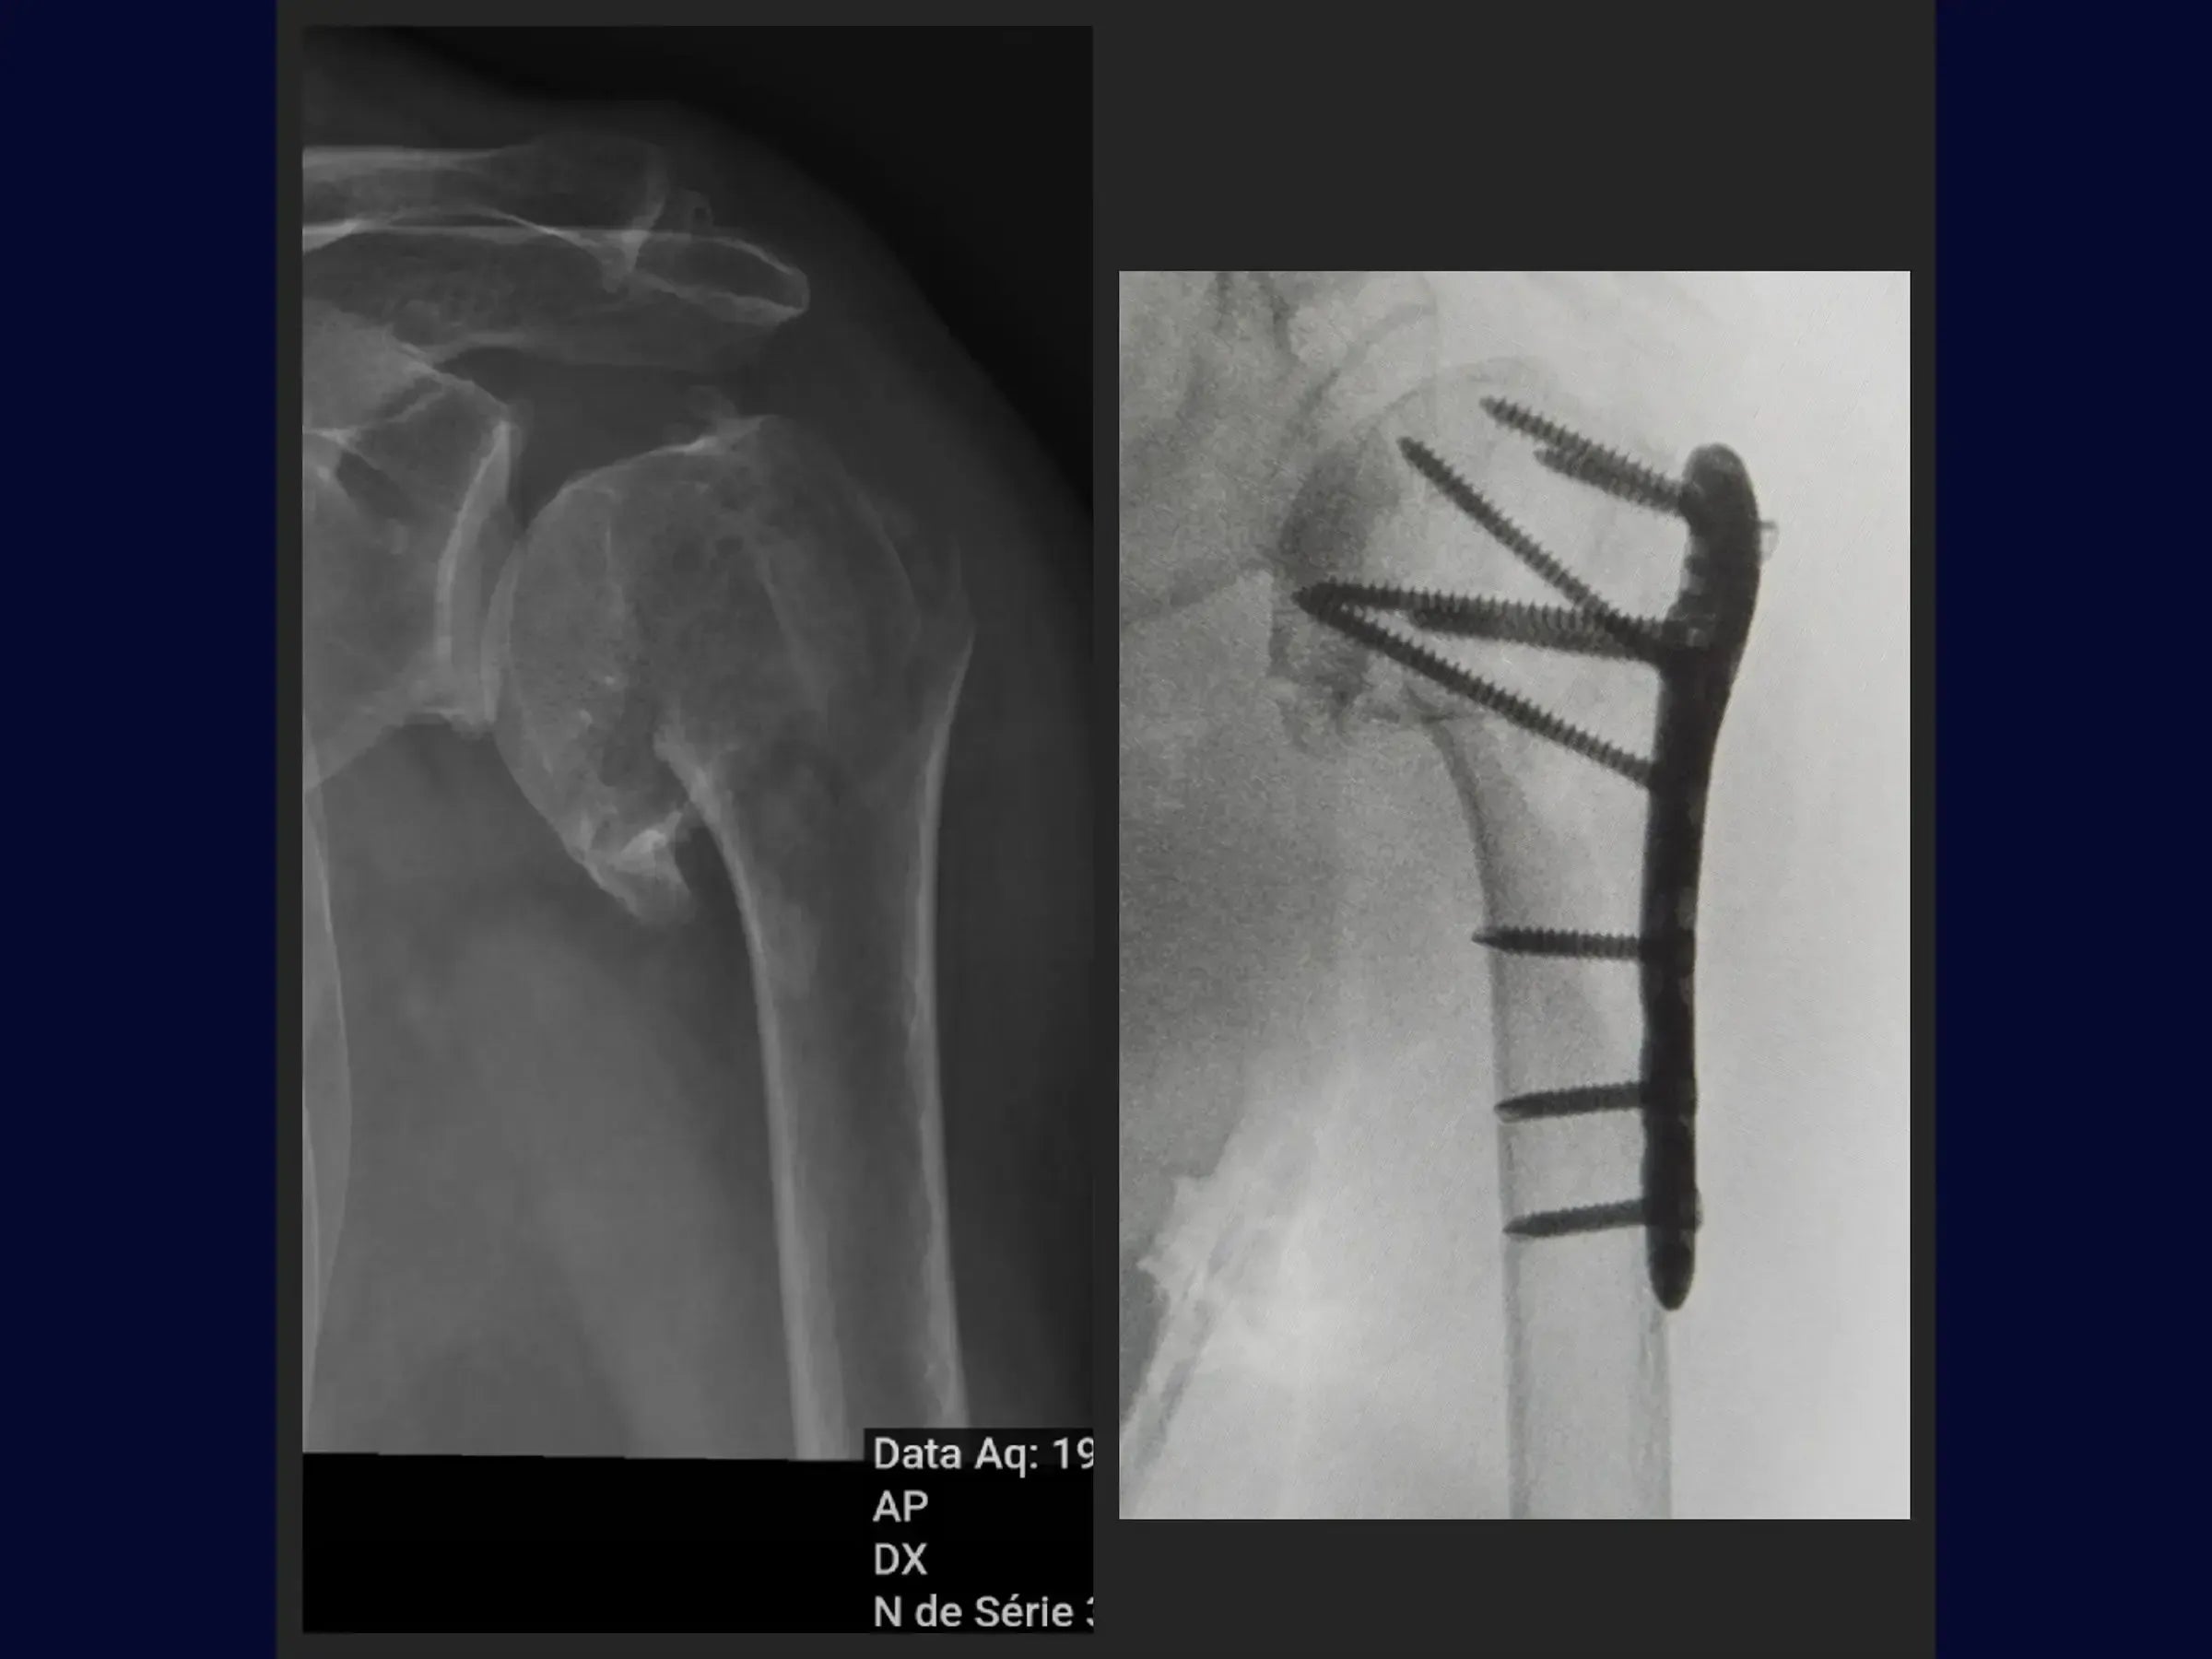

Domine o tratamento de fraturas do úmero proximal. Este treinamento oferece uma imersão técnica na osteossíntese com placa via acesso deltopeitoral, apresentada em vídeo 4K sob a perspectiva do cirurgião, abordando o manejo em pacientes idosos com artrose glenoumeral assintomática.

- Osteossíntese de fraturas do úmero proximal com placa.

- Fixação com placa e posicionamento de parafusos.

- Redução da Fratura Guiada: Abordagem sistemática para redução da fratura utilizando manipulação do braço e laçadas, com pontos de referência anatômicos como o sulco do bíceps e vértices da fratura para controle de alinhamento e rotação.

- Avaliação Intraoperatória Detalhada: Análise radiográfica para verificação da altura da placa, redução da fratura e centralização da placa, assegurando a distribuição adequada dos parafusos.